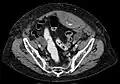

A rectus sheath hematoma is an accumulation of blood in the sheath of the rectus abdominis muscle. It causes abdominal pain with or without a mass.